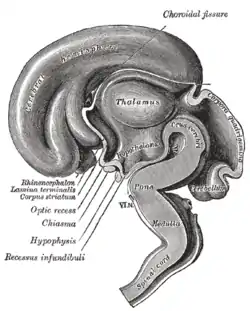

Median sagittal section of brain of human embryo of three months. (Lamina terminalis labeled at center left.) | |